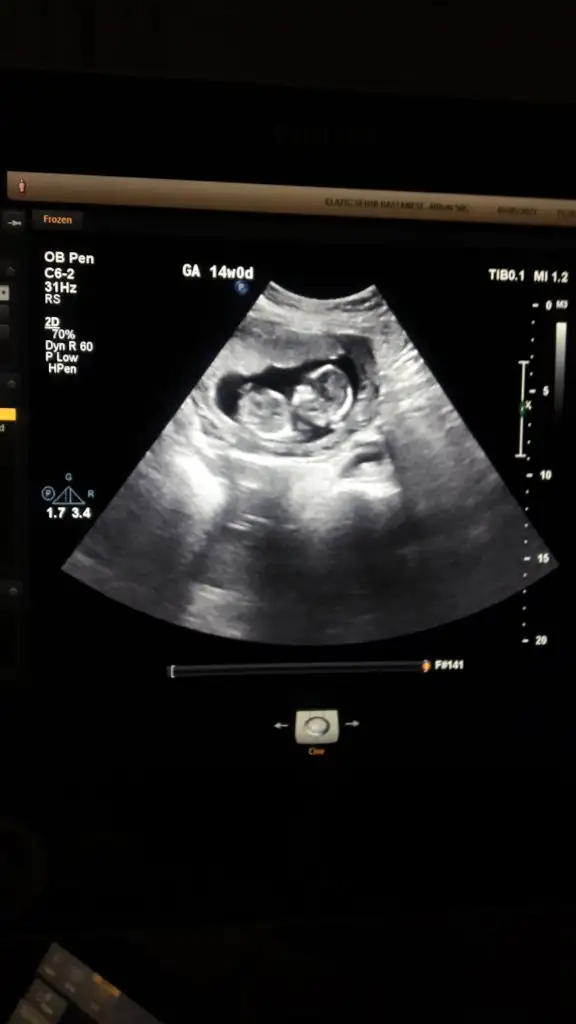

Bebegin Kesedeki Konumuna Göre Cinsiyet Tahmini